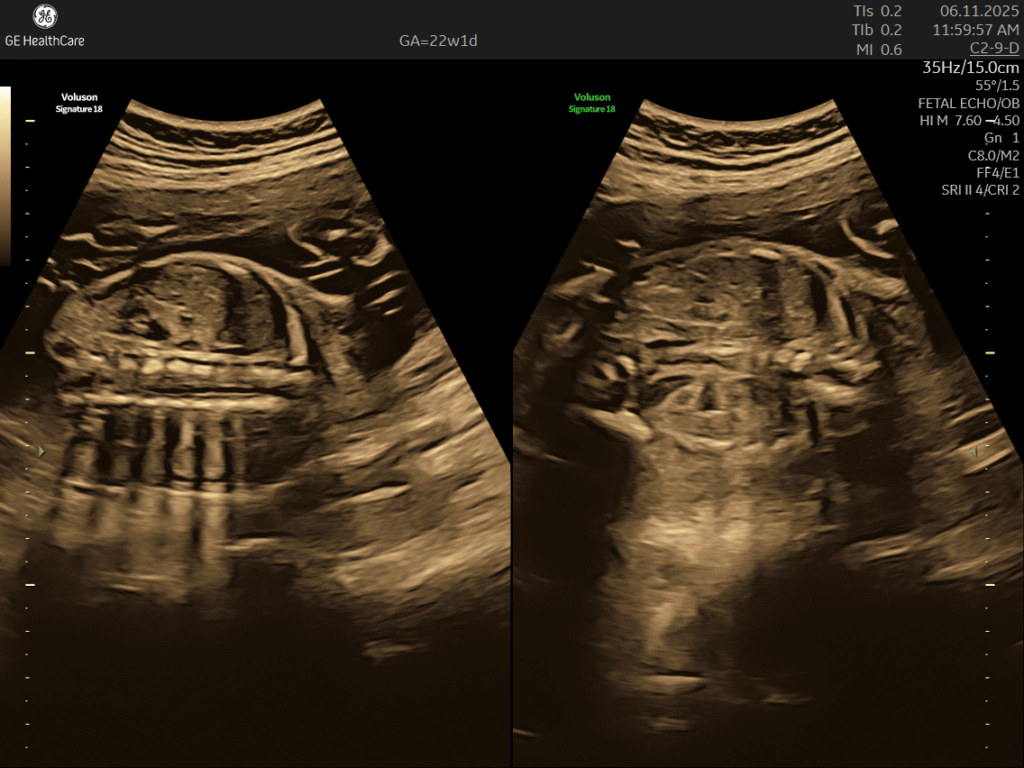

Fetal Echocardiography (22–26 weeks GA)

Fetal Echocardiography in kolkata Fetal echocardiography is a valuabe early screening tool for Fetal Heart Defects. It is a specialized

Precision Diagnostics powered by state-of-the-art GE Voluson systems designed for women and prenatal care.